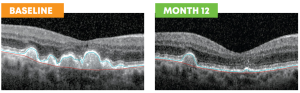

Before treatment at Baseline, there were piles of waste-like material (drusen) under the retina, which can damage vision over time. After PBM therapy, those piles shrank, the retina looked smoother and healthier, and the patient’s vision even improved — they could read 4 more letters on the vision chart at Month 12.